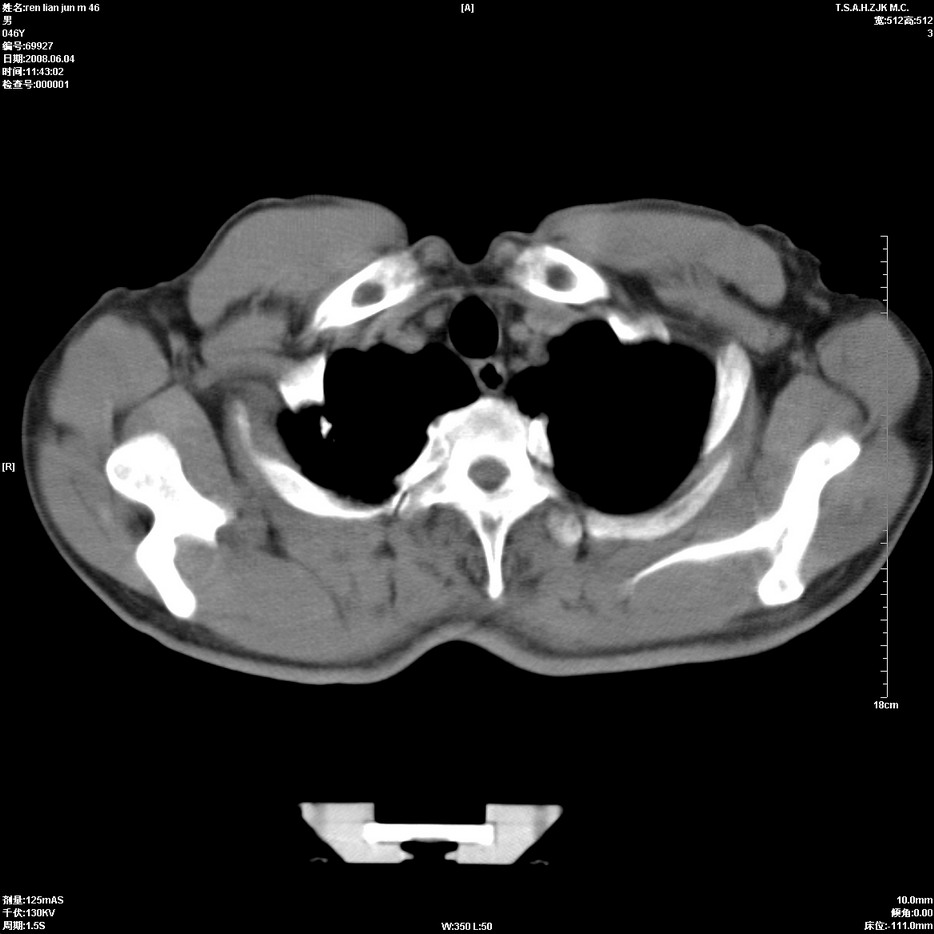

以下是引用形影不离在2008-6-5 19:18:00的发言:[br]右肺中心型肺癌并纵隔及左侧腋窝淋巴结转移,颅内应做增强检查。